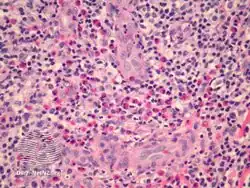

Epithelioid haemangioma is a non-cancerous tumor typically found in skin and soft tissue of usually the head and neck region, where it presents with reddish-pink itchy painful bumps.[1] It can occur in bone as a type of vascular tumor of bone, where it can give rise to pain and swelling.[2]

It is made up of well-formed blood vessels lined by lymphocytes and eosinophils (types of white blood cells).[1]